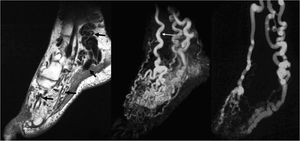

MRI is usually required for definitive diagnosis and extent evaluation. As opposed to hemangiomas, AVMs usually present as ill defined non-mass like lesions infiltrating multiple tissue planes. High-flow large feeding arteries and draining veins are seen as tangles of serpiginous signal voids on SE images (Figs. 4 and 5), high-signal intensity foci on GRE Images 9,27 and intense contrast enhancement (Figs. 4 and 5). Areas of T1 hypointensity within the bone marrow reflect intraosseous extension of the lesion.13 Additional intralesional areas of T1-shortening may represent hemorrhage or thrombosis.20 Contrast-enhanced MRA in the arterial and venous phases with multi-planar reconstruction are useful for detailed anatomic display of the feeding arteries and draining veins (Fig. 6). Time-resolved dynamic 3D MRA permits excellent assessment of the hemodynamics of the components of the AVMs, including the nidus. Early venous shunting is a characteristic 9,27 (Figs. 4–6). Accurate characterization of the lesion is further achieved with conventional arteriography which, in addition, can be used for assessment of the feasibility of endovascular treatment and subsequent therapy.

35-Year-old female with AVM within the left foot. Enlarged high-flow feeding arteries, draining veins, as well as the nidus of the AVM are seen as signal voids on FSE images (a) (arrows). Arterial phase MRA (b) depicts the arterial supply of the AVM, primarily by a tortuous and dilated dorsalis pedis artery (thin arrow), as well as early filling of the nidus (asterisk), and the draining veins (arrowheads). Excellent correlation with catheter angiography (c).